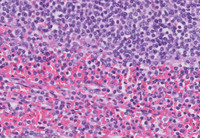

Figure 4: H&E Images of Histology in Splenic Marginal Zone Lymphoma

Whole slide scanned image (pictured on the upper left) demonstrating multiple nodules throughout the splenic parenchyma.

At medium power (pictured on the upper right), the nodules comprise markedly expanded white pulp areas.

At higher power (pictured on the lower left) at the interface of the white pulp and red pulp, the nodular areas of the white pulp comprised monotonous small lymphoid cells with monocytoid cytomorphology. Note that the red pulp at the bottom is relatively uninvolved.